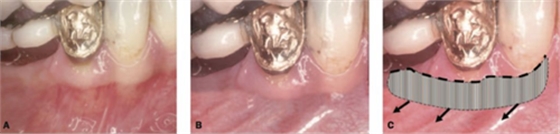

傳統(tǒng)的縫合方式非常簡單,比如:

該方式齦瓣固定的效果差,術后血供差,為了改善血供,我們提倡下面的改良縫合方式,血供更好,成功率更高,如下圖:

通過用縫線壓迫的方式固定,術后愈合的過程齦瓣始終與受區(qū)骨膜貼合,而不會移動。